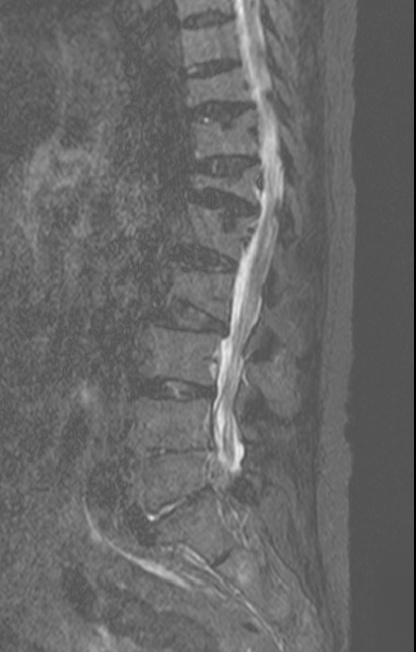

-L Spine MRI

-심한 과호흡 상태에서 검사 시행

-검사 도중 계속 움직임

-Motion Artipact 심하여 scan time 짧게 조정함.

- L2-3, L3-4 and L5-S1 diffuse bulging discs and ligamentum flavum thickening with indentation of thecal sac and encroachment on neural foramens

- some CSF effacement of L2-3 and L3-4 thecal sac

- partial to circumferential perineural fat effacement of left L5-S1 neural foramen

1. old T10 through L2 compression fracture with schmorl's nodes

2. L2-3, L3-4 and L5-S1 diffuse bulging discs

3. mild L2-3 and L3-4 central stenosis

4. moderate stenosis of left L5-S1 neural foramen

5. degenerative spondylosis